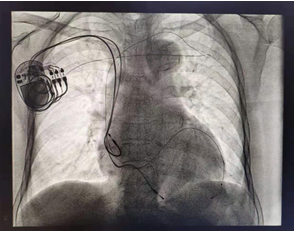

近日,我院心血管内三科成功开展一例三腔起搏器CRT(心脏再同步治疗)植入术,此手术在我市尚属首例,为扩张型心肌病、严重心力衰竭患者的心功能改善提供了新的有效的治疗方法。

患者是一位72岁高龄的女性,既往有心动过缓、心肌病、心力衰竭等心脏病史,并于12年前行双腔起搏器植入术。患者平素心衰反复发作并多次进入ICU抢救,近日因体内起搏器电耗竭,病情日趋严重,入住我院心血管内三科进一步治疗。心内三科为老人完善各项相关检查,显示患者为重度心力衰竭,心脏明显扩大,心功能指标大幅度下降,合并完全性左束支传导阻滞,左右心室收缩不同步。老人之前体内植入的双腔起搏器,主要针对的是慢性心律失常疾病的患者,无法治疗心力衰竭的病症,而传统的药物治疗效果不理想。考虑到患者情况,心内三科杜建军主任与科室治疗团队对患者病情进行了多次讨论,认为更换升级为三腔起搏器CRT是治疗此类患者的最好方法。在征得患者及家属同意并做好了充分的术前准备后,手术如期进行,患者在局部麻醉下经过2小时手术,顺利植入三腔起搏器CRT,术后各项参数检测正常。目前,患者恢复良好,心功能得到明显改善。

据杜建军主任介绍,15%的心衰患者有左、右心室之间及左心室内部收缩不协调的情况,这就导致已经心衰的患者的心脏工作效率急剧下降,心脏不能作为一个完整的合苞体完成射血动作,从而加速心脏恶化的进程。三腔起搏器CRT(心脏再同步治疗)除常规右心房、右心室起搏外,还需要另外放置一根起搏线到左心室的特殊位置,使得心房和心室之间的收缩更加协调,左右心室保持同步一致,从而达到改善心力衰竭症状的目的。国内、外大量研究表明,该疗法不仅可以恢复心脏同步,还能明显改善心脏功能,降低死亡率,但该手术操作难度很大,对医生技术要求较高。此次病人为高龄久病患者,既往曾行双腔起搏器植入术,更增加了手术难度。此次手术的成功开展,充分体现了我院心内科团队过硬的技术实力和勇于担当的高尚医德,诠释了我院医务工作者不畏挑战、创新求精的职业精神,标志着我市在重度心力衰竭的诊断与治疗方面迈上了新的台阶,心衰治疗领域已达到国内领先水平。